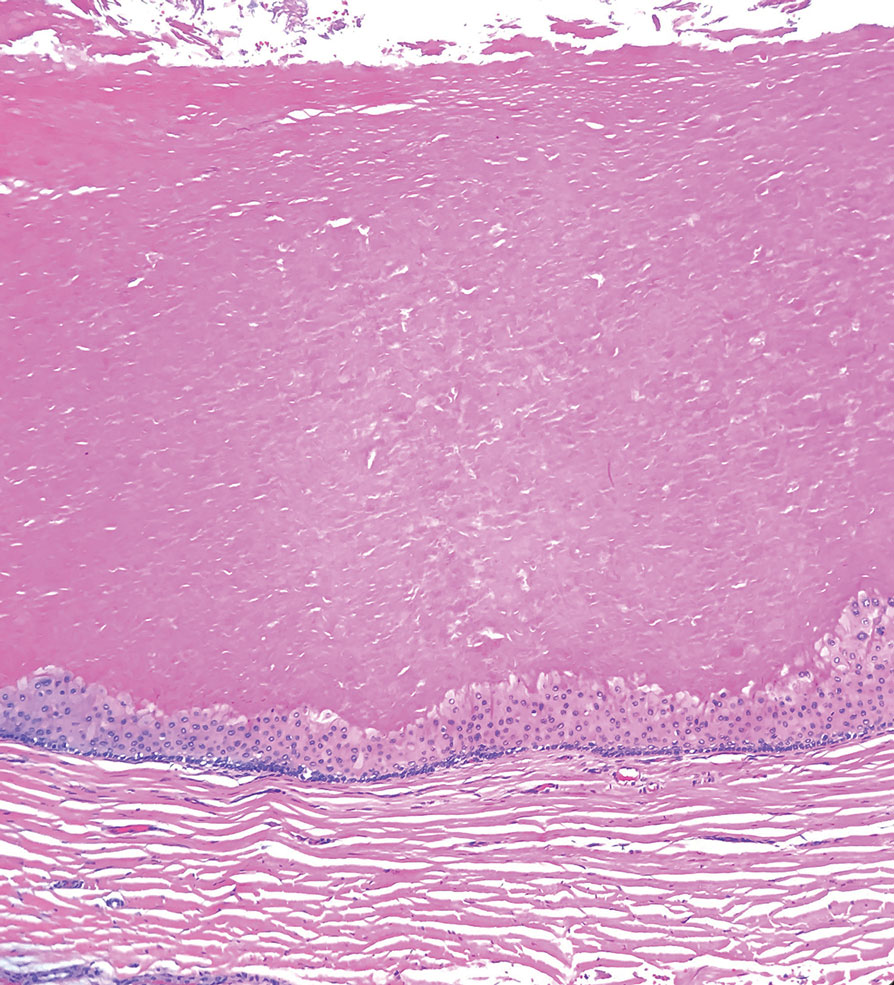

T he biopsy results confirmed the diagnosis of spiradenocylindroma with negative margins. At 6-week follow-up, the patient had no signs of recurrence. Spiradenocylindroma is a benign hybrid neoplasm consisting of histologically intermixed areas representing the spectrum of morphology between spiradenoma and cylindromas.1,2 Both spiradenoma and cylindroma comprise 2 distinct populations of dark and pale basaloid cells.2,3 The spiradenomatous areas of the spiradenocylindroma are arranged in large, well-circumscribed collections of small, darkly staining cells with interspersed lymphocytes and a thin basement membrane surrounding spiradenocylindroma component.2,3 The spiradenocylindroma regions also may contain tubular structures dilated by hemorrhage.2 In contrast, the cylindromatous regions have a jigsaw-puzzle configuration of polygonal tumor nests containing peripherally palisading dark cells and central pale cells, surrounded by a thick basement membrane (top quiz image).2,3